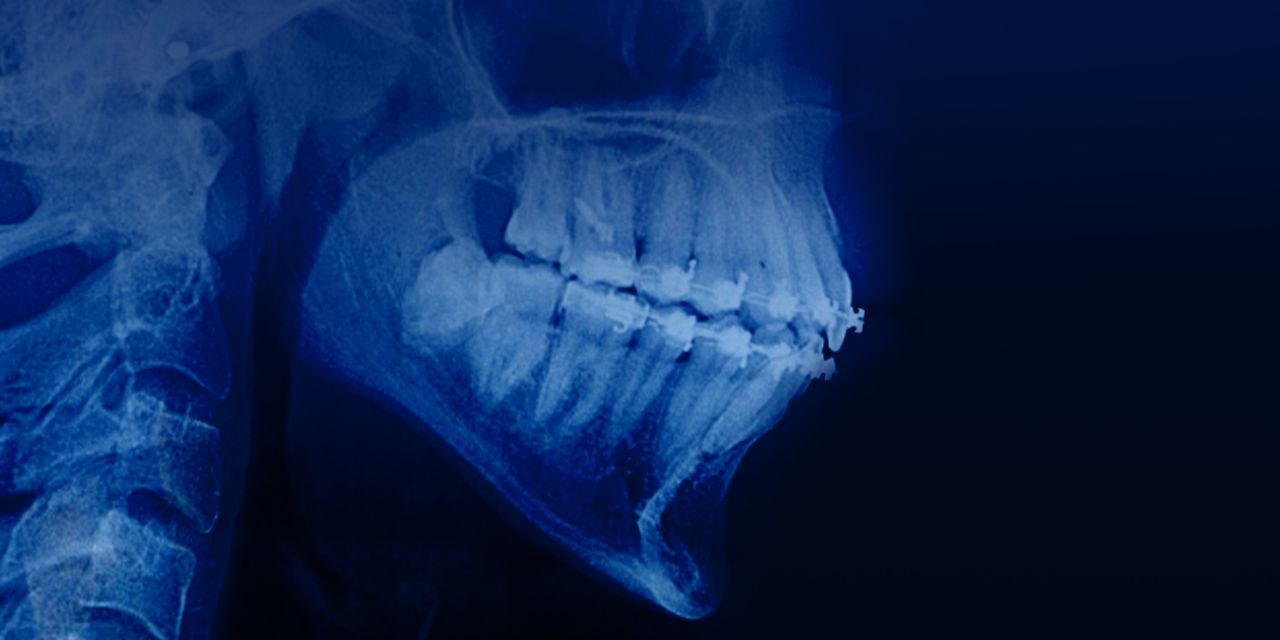

Periodontal patients with Invisalign system

– Treatment of patients with periodontal diseases: advantages of aligner therapy